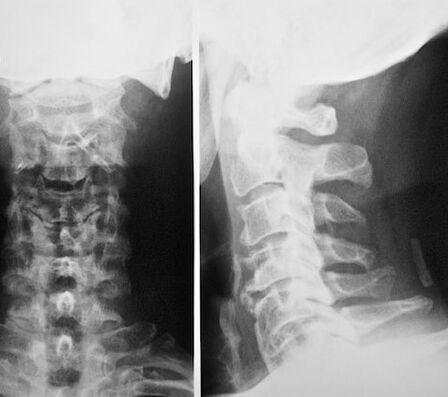

Dzemdes kakla nodalījumam ir sarežģīta struktūra, un tā sastāv no 7 skriemeļiem, no kuriem katrs veic vairākas funkcijas: atbalsta galvu, pagriežas, saliec kaklu un citas svarīgas funkcijas. Starp skriemeļiem ir starpskriemeļu diski, kas padara mugurkaulu elastīgu un izturīgu, un paši starpskriemeļu diski sastāv no šķiedru gredzeniem, kuru iekšpusē ir pulpētie kodoli. Dzemdes kakla skriemeļi ir tuvu viens otram, tāpēc pat nelielas fiziskās aktivitātes var izraisīt to pārvietojumu, kas savukārt izraisa asinsvadus un nervus. Dzemdes kakla mugurkaulā ir mugurkaula artērijas, kas ir atbildīgas par smadzeņu asiņu piegādi. Saspiežot tos, asins piegāde tiek traucēta, smadzenes nesaņem pietiekamu daudzumu dzīvībai svarīgu vielu, kas neapšaubāmi noved pie tā sakāves un attīstības daudzām komplikācijām, kas var izraisīt pacienta invaliditāti vai pat nāvi.

Dzemdes kakla osteohondroze - simptomi un ārstēšana tieši ir atkarīga no bojātā nervu mugurkaula. Dzemdes kakla sakņu skaits ir 8, un dzemdes kakla skriemeļi ir 7. Katrs dzemdes kakla nervs atrodas virs skriemeļa, un ar bojājumiem ir savi simptomi.